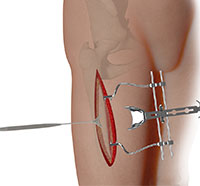

Arthroscopy, also referred to as keyhole or minimally invasive surgery, is a procedure in which an arthroscope is inserted into a joint to check for any damage and repair it simultaneously.